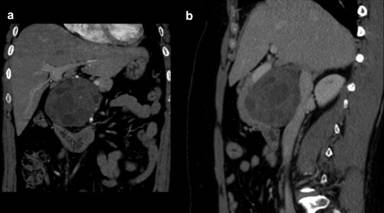

A 49-year-old woman presented with two years of intermittent epigastric pain. The episodes typically lasted a few days and were associated with nausea and anorexia. Her past medical, surgical, social and family history were non-contributory. Physical exam was only remarkable for a body mass index of 33 kg/m2, and common laboratory values were within normal range. A triple-phase CT demonstrated an 8.5 cm head of the pancreas mass with both solid and cystic components displacing the duodenum and pancreas anteriorly, and the vascular structures medially (Figure 1). There was no biliary or pancreatic ductal dilatation, and chest and liver imaging were unremarkable. The patient was subsequently referred to our hospital for further evaluation, at which time CA 19-9 and carcinoembryonic antigen levels were found to be normal. Endoscopic ultrasonography demonstrated a head of the pancreas mass with both solid and cystic components, thickened cyst walls, a fat plane between the vascular structures, and no suspicious lymphadenopathy. Fine needle aspiration revealed mucin, and benign cytology.

Figure 1. Coronal (a.) and sagittal (b.) views of an 8.5 cm head of the pancreas mass. |